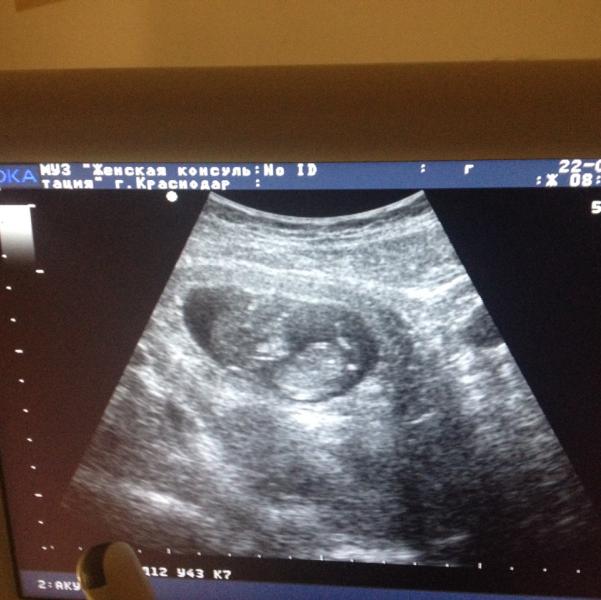

Наше второе маленькое счастье:) сказали все хорошо, красивый, здоровый малыш)

@sid_ka_, :) сказали вроде пацан, а так фиг его рано ещё)